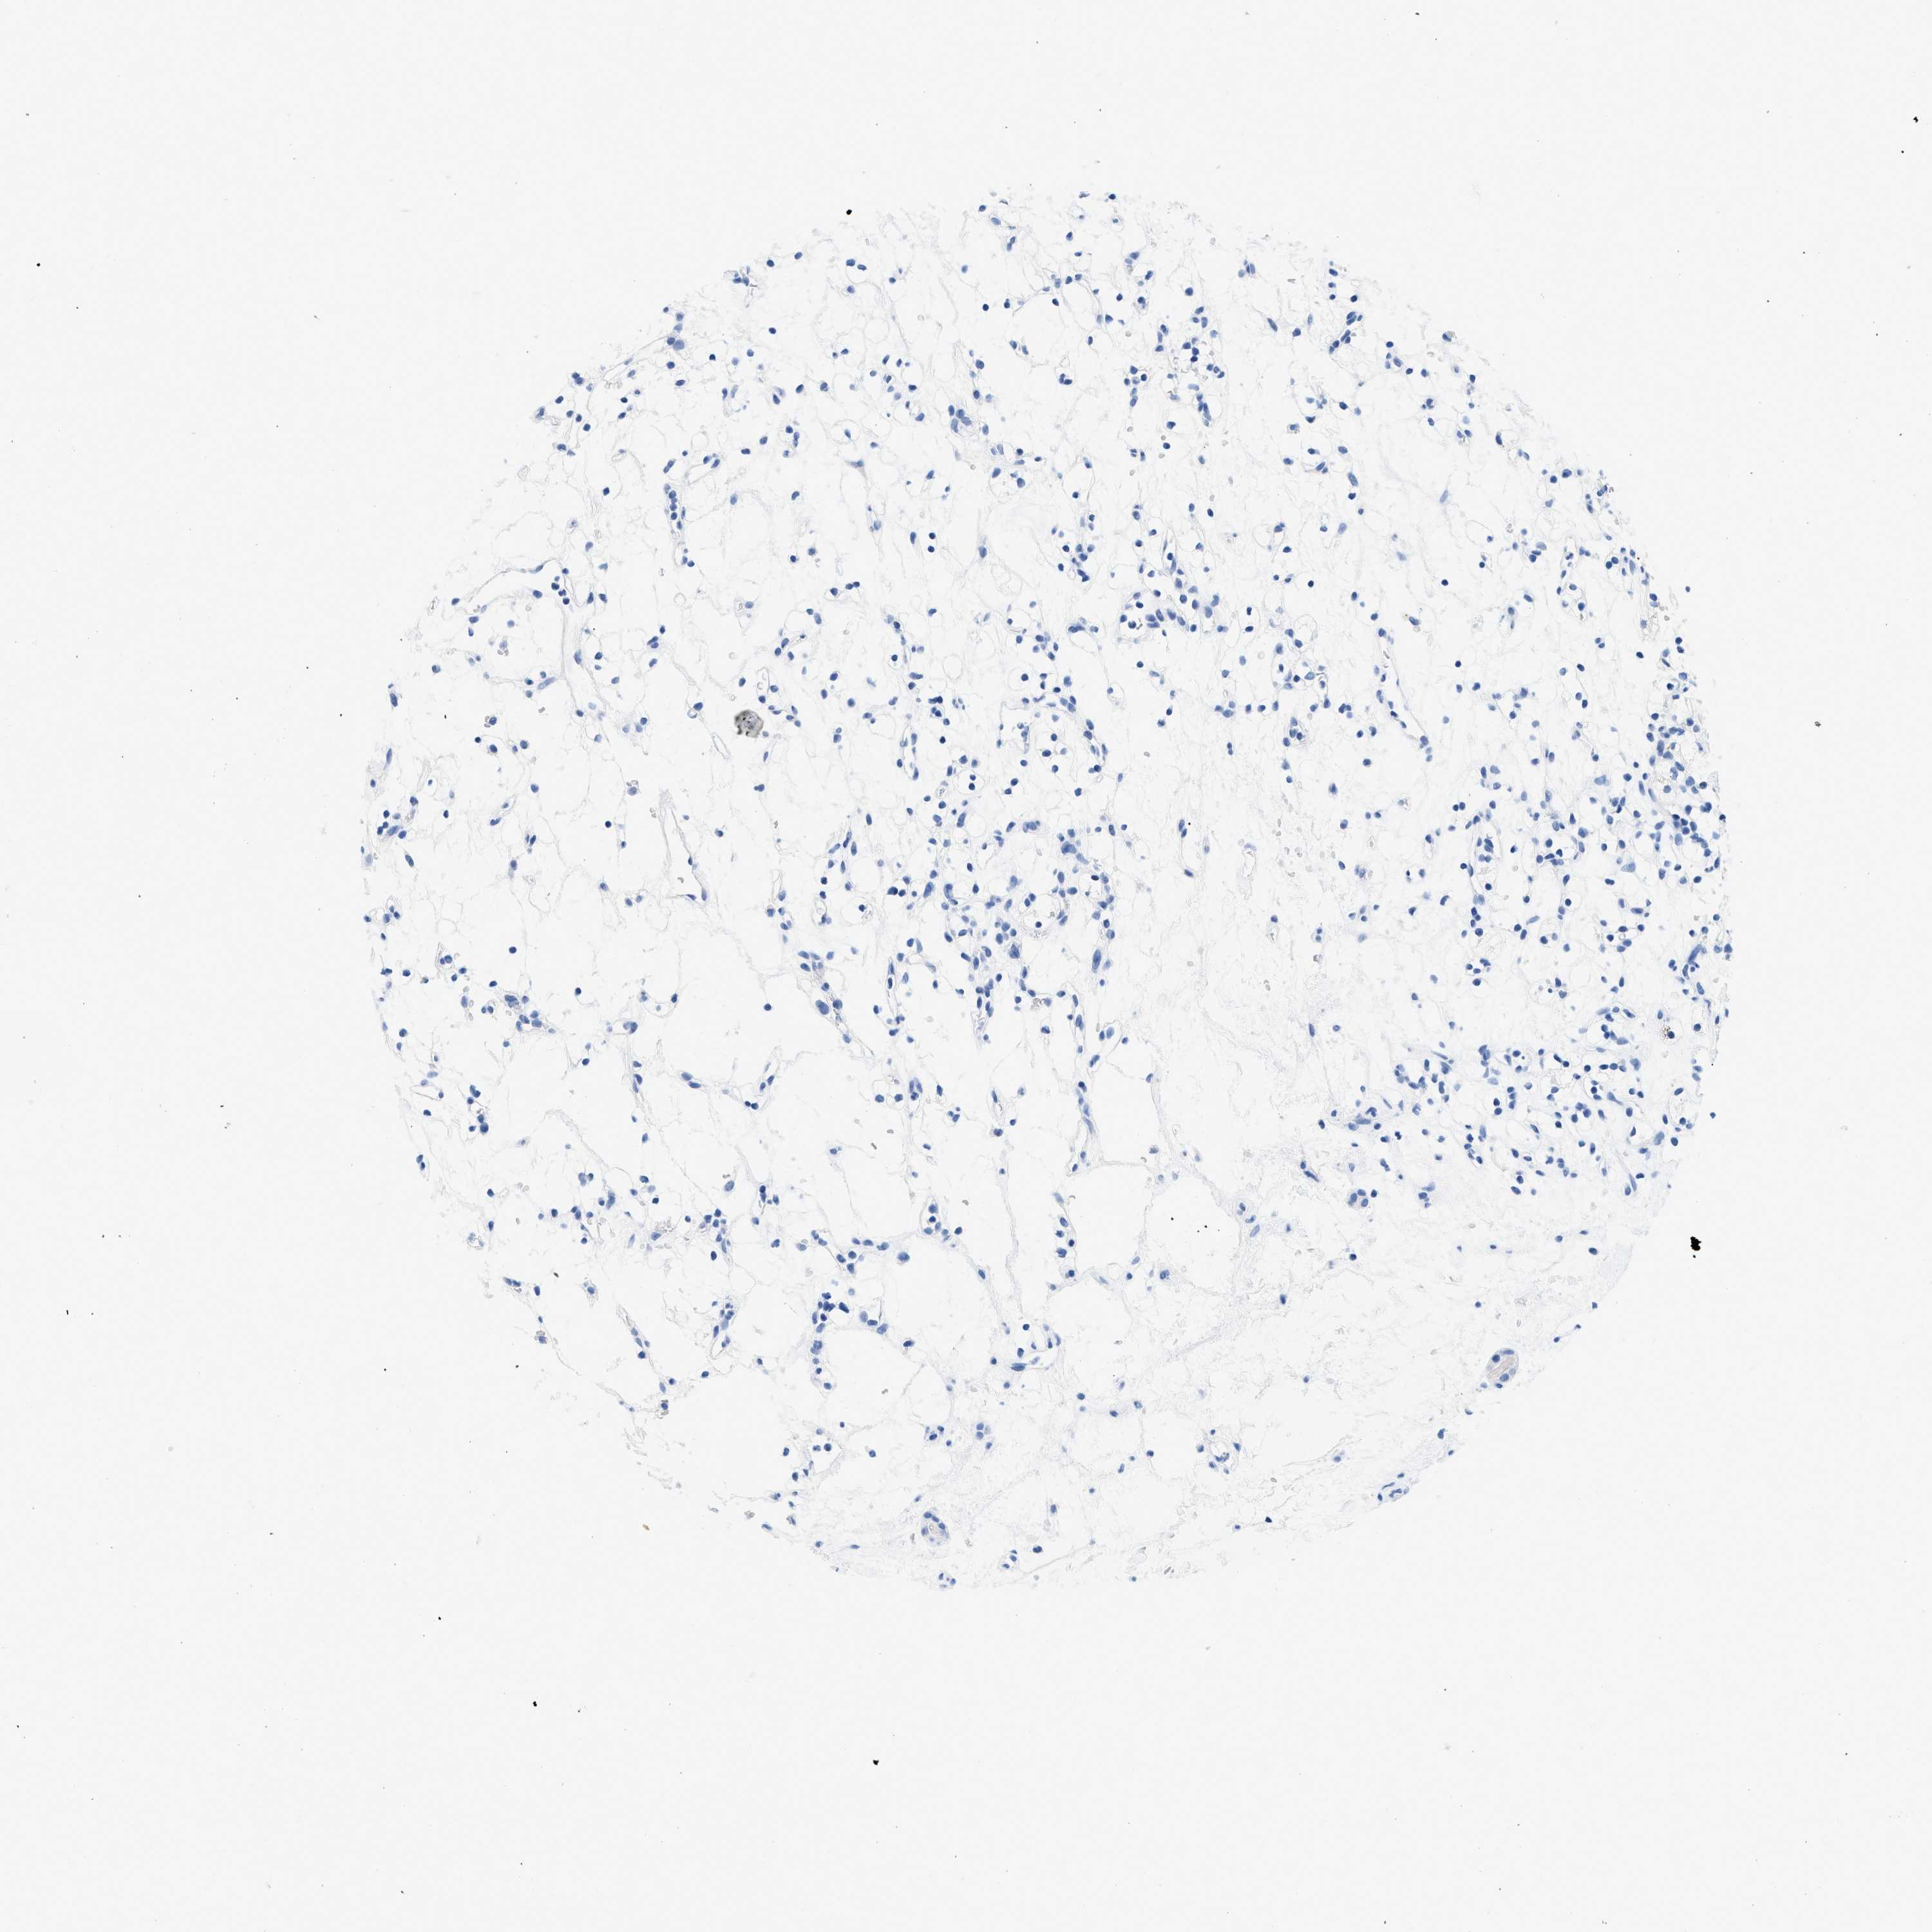

KIDNEY RENAL CLEAR CELL CARCINOMA (VALIDATION) - Interactive survival scatter ploti

The Survival Scatter plot shows the clinical status (i.e. dead or alive) for all individuals in the patient cohort, based on the same data that underlies the corresponding Kaplan-Meier plots. Patients that are alive at last time for follow-up are shown in blue and patients who have died during the study are shown in red.

The x-axis shows the expression levels (FPKM) of the investigated gene in the tumor tissue at the time of diagnosis. The y-axis shows the follow-up time after diagnosis (years). Both axes are complimented with kernel density curves demonstrating the data density over the axes. The top density plot shows the expression levels (FPKM) distribution among dead (red) and alive patients (blue). The right density plot shows the data density of the survived years of dead patients with high and low expression levels respectively, stratified using the cutoff indicated by the vertical dashed line through the Survival Scatter plot. This cutoff is automatically defined based on the FPKM cutoff that minimizes the p-score. The cutoff can be changed by dragging the vertical line or by entering a cutoff value in the square labeled "Current cut-off".

Under the Survival Scatter plot the p-score landscape (black curve; left axis) is shown together with dead median separation (red curve; right axis). Dead median separation is the difference in median mRNA expression between patients who have died with high and low expression, respectively. It is calculated as follows: median FPKM expression of dead patients with high expression - median FPKM expression of dead patients with low expression. This is intended to aid the user in visually exploring custom cutoffs and the associated p-scores and dead median separation.

Individual patient data is displayed and can be filtered by clicking on one or more of the category buttons on the top of the page. Categories describing expression level and patient information include: high, low, alive, dead, female, male and tumor stages. The scale of the x-axis can be toggled between linear and log-scale by clicking on the "x log" button. Mouse-over function shows TCGA ID, patient information and mRNA expression (FPKM) for each patient.

& Survival analysisi

Kaplan-Meier plots summarize results from analysis of correlation between mRNA expression level and patient survival. Patients were divided based on level of expression into one of the two groups "low" (under cut off) or "high" (over cut off). X-axis shows time for survival (years) and y-axis shows the probability of survival, where 1.0 corresponds to 100 percent.

GSN is validated prognostic, high expression is favorable in Kidney Renal Clear Cell Carcinoma (validation)

: 192.95

Average pTPM 309.2

Number of samples 100